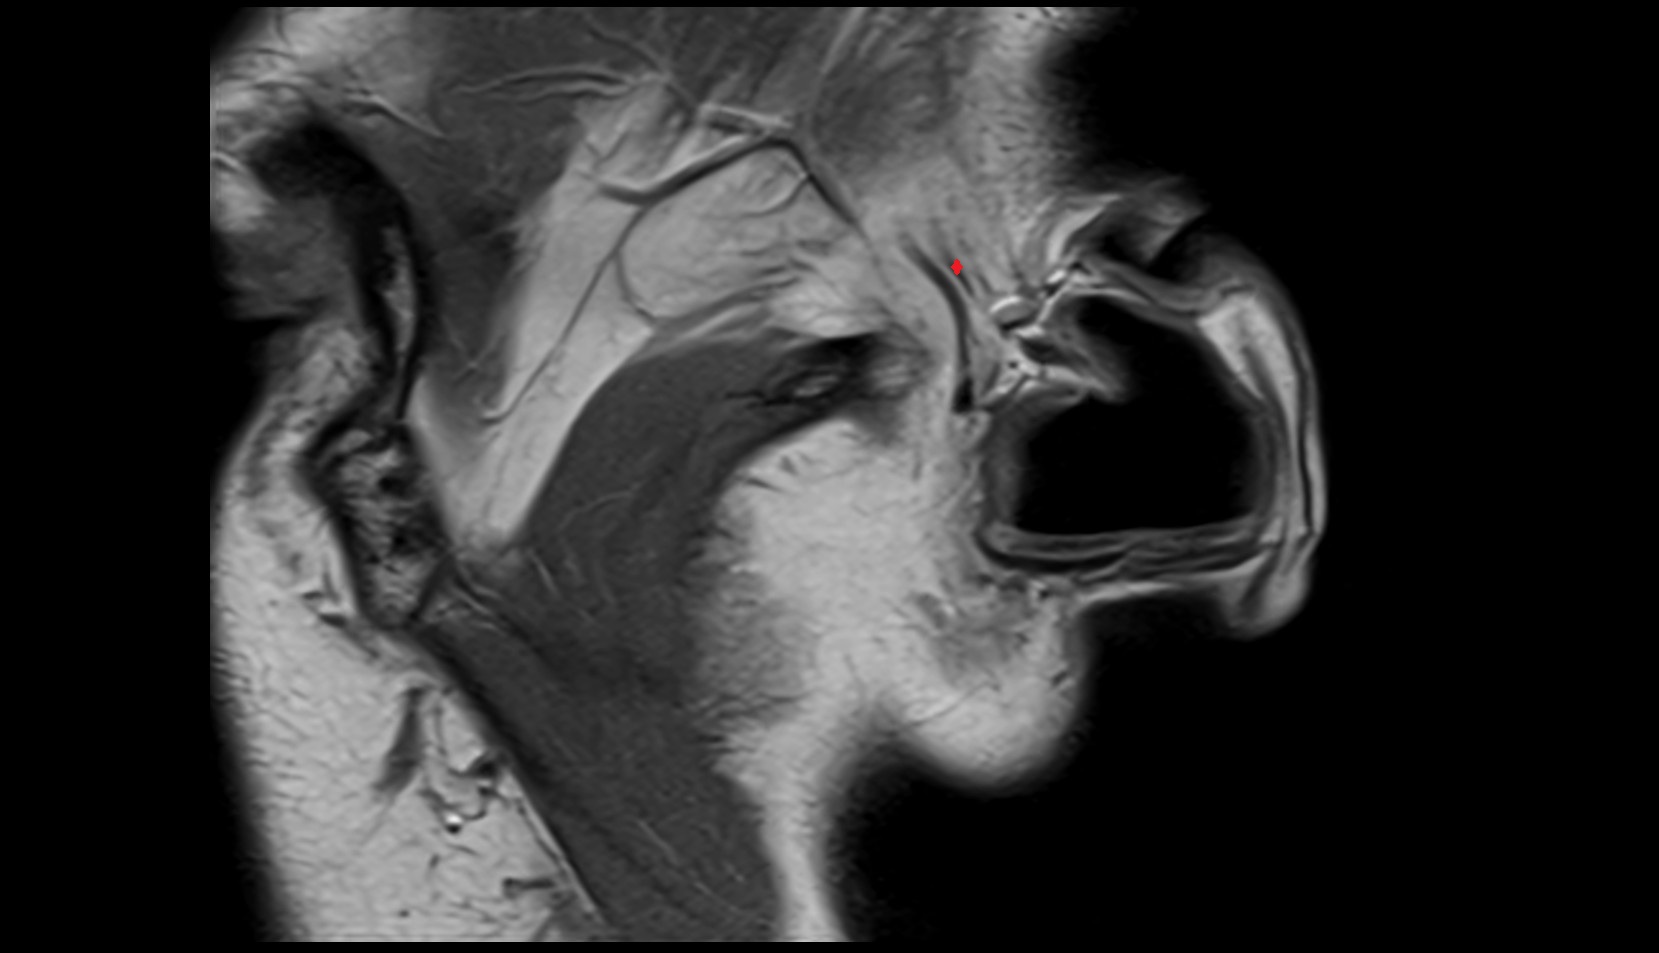

- Temporomandibular joint

- Mandibular condyle

- Mandibular fossa

- Articular disc of temporomandibular joint

- Articular eminence

- Superior head of lateral pterygoid muscle

- Inferior head of lateral pterygoid muscle